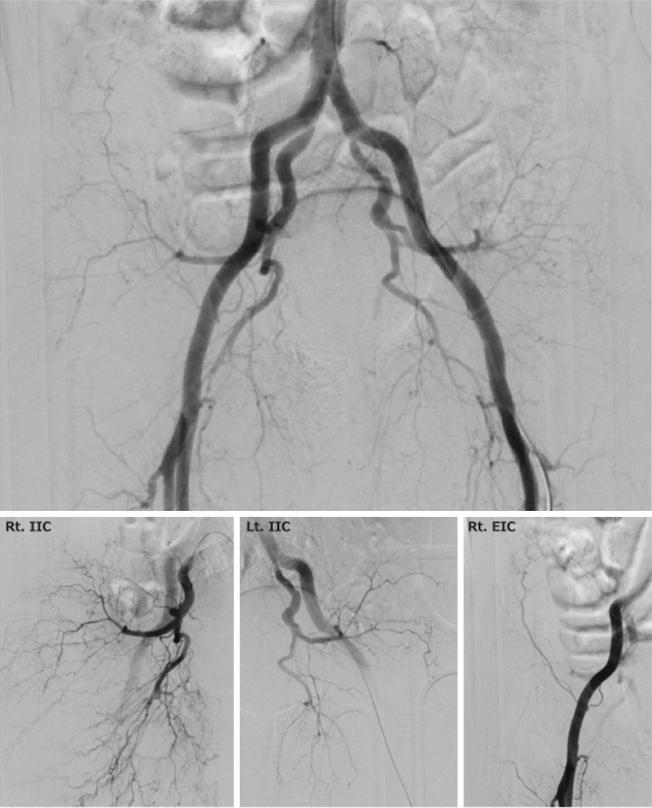

Visualized Efficacy of Andexanet Alfa in an Elderly Trauma Patient with an Unstable Pelvic Fracture.

JMA J. 2024 Jul 16;7(3):438-440. doi: 10.31662/jmaj.2024-0007. Epub 2024 Jun 3.

DOI:10.31662/jmaj.2024-0007

PMID:39114625

原文链接:https://pmc.ncbi.nlm.nih.gov/articles/PMC11301022/